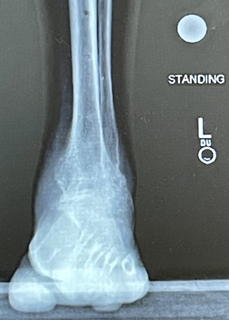

When the fixator was removed, I had to wear a cast for several weeks and then a boot for another pair of weeks. My mood and outlook began to change. My ankle and foot felt strong, straight, and flat! After the removal of the boot, my wife and I went to diner to celebrate! I haven’t felt as confident in a long, long time! I do not have any pain. I am so very happy with the correction and greatly improved quality of life that Dr. Rozbruch has given me. It was so much fun to mow the lawn and work in the garden again!

My left foot is now like my right for the first time in my life! I can even run for the first time in years!